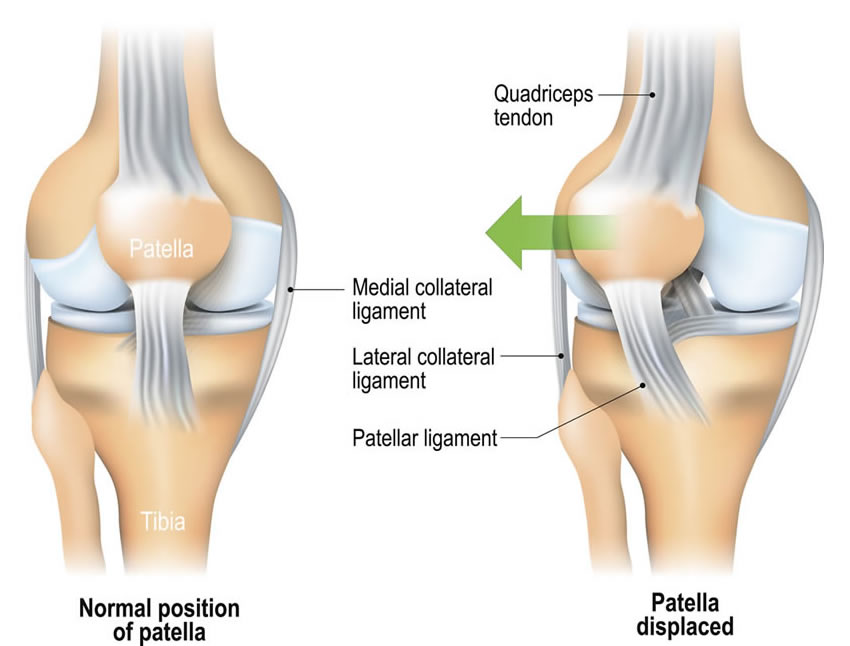

Recurrent Patellar instability is a phenomenon in which the patient suffers from multiple patellar dislocations, subluxations or a sense of instability.

The dislocations are almost always directed towards the outer side, and there is a clear history of an episode of instability (described as a deformity of the knee) followed by reduction either spontaneously or after manipulation.

History of the knee giving away or more specifically the “Knee Cap” giving away or moving outwards should arouse the suspicion of possible patellar instability. The initial episode is almost always following a traumatic fall especially while playing.

This is followed by sensation of instability with or without pain and may be aggravated during certain day to day activities like getting up from a sitting position, coming down the stairs or while pivoting, as one may do while abruptly making a sharp turn outward. The second and subsequent dislocations might be traumatic but lesser force is required to dislocate the patella.